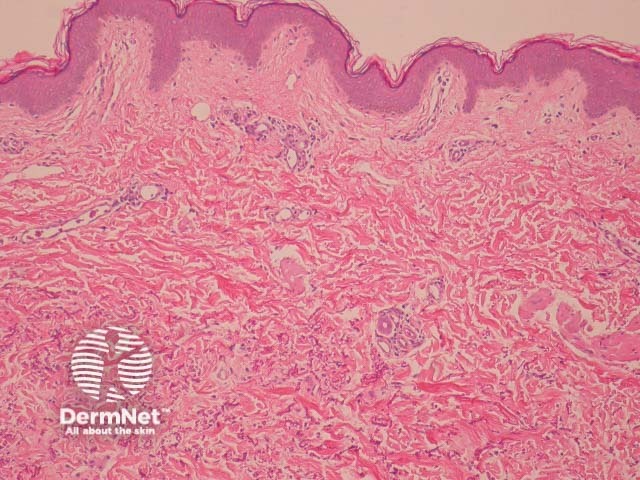

In PXE, elastic fibres of the reticular dermis are short and fragmented. The abnormal fibres are basophilic and evident on H-E sections. Rarely, the abnormal fibres elicit a granulomatous reaction (figures 1, 2, 3).

Figure 1